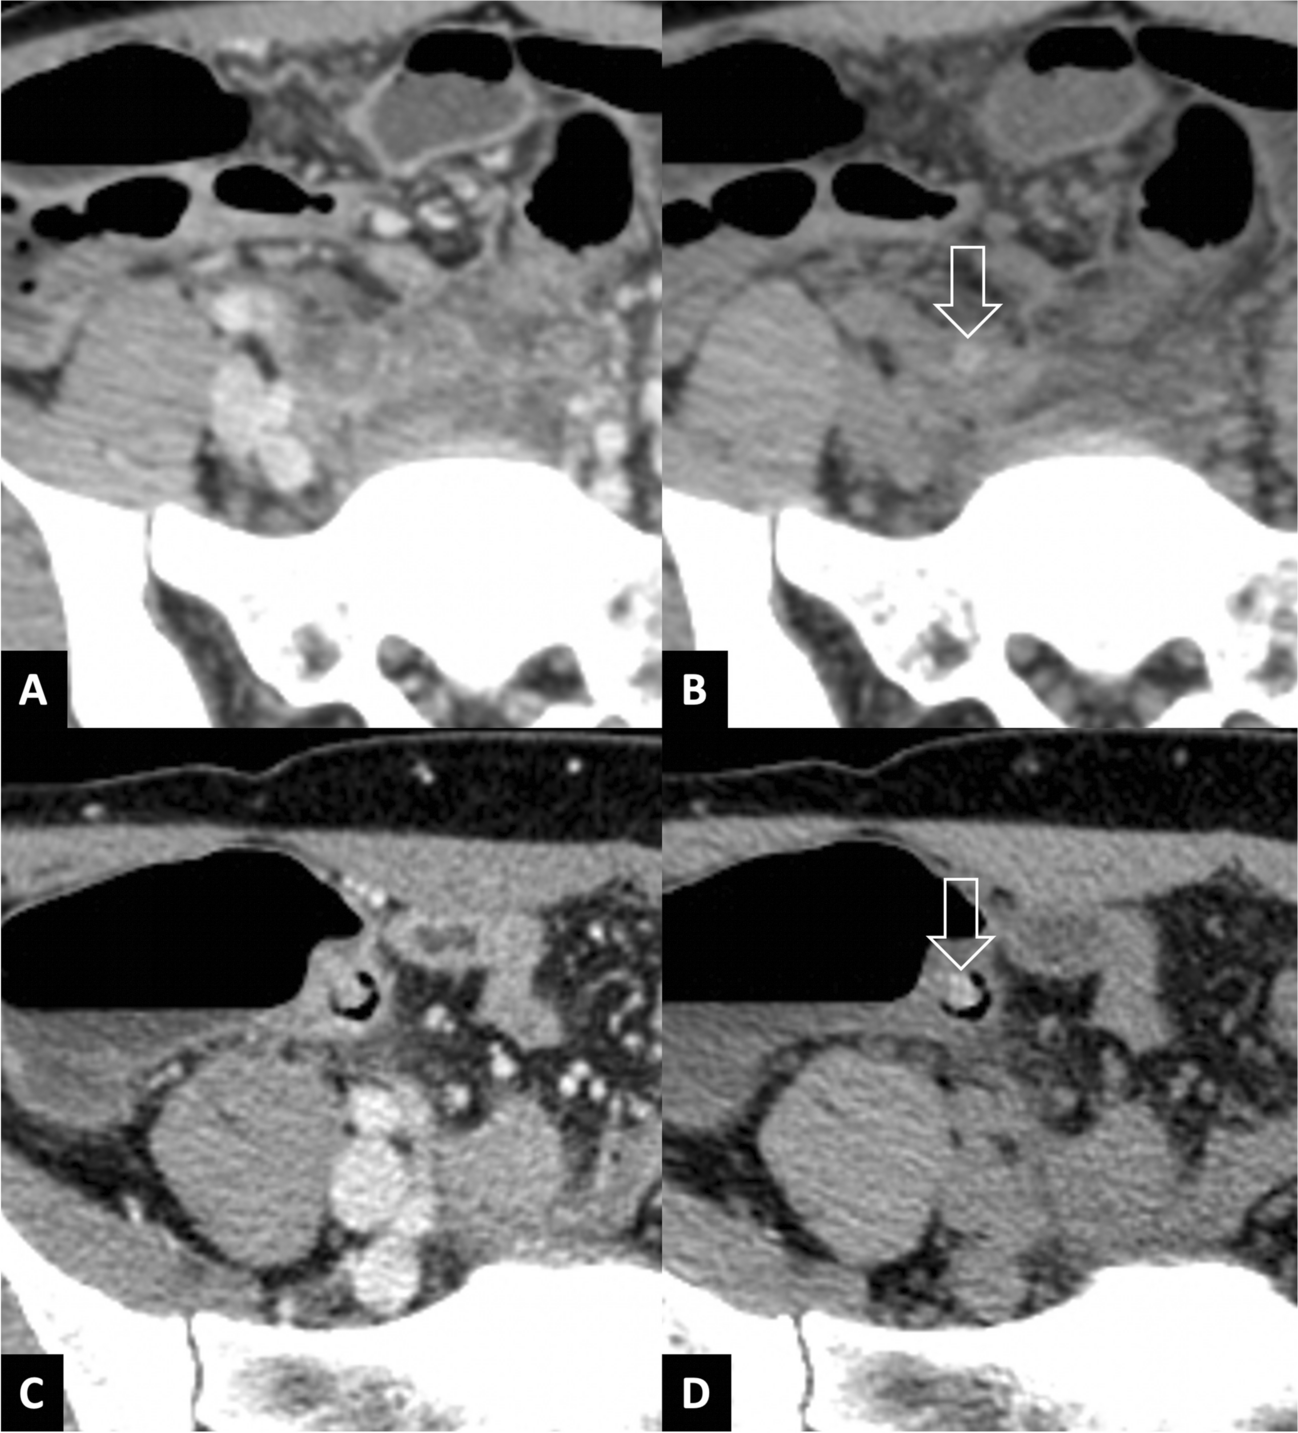

Twenty-four patients had 28 appendicoliths not detected on the portovenous phase (Fig. 4, Supplementary Material 3). Among these 24 patients, 16 had complicated appendicitis as confirmed by histopathology or surgical operative findings. CT correctly identified complications in 14 patients, while 5 were correctly identified as not having complications. There were 2 false negatives and 3 false positives during the re-review of CT images.

Fig. 4

Example of two cases with appendicoliths (arrows) undetected on portovenous-phase CT (A, C) but visible on noncontrast CT (B, D)

This investigation highlights the importance of identifying appendicoliths in adult appendicitis due to their association with complications, like gangrene or perforation, as well as significantly longer hospital stays. The only CT characteristic of appendicolith significantly associated with increased likelihood of complicated appendicitis was the larger minimum diameter of appendicoliths. The sensitivities of portovenous-phase CT in detecting appendicoliths were 82.1% per patient and 88.2% per appendicolith. Unsurprisingly, these undetected appendicoliths had a small minimum diameter and a homogeneous appearance, and were less distinguishable from surrounding soft tissues. These overlooked appendicoliths, however, resulted in misclassification of acute appendicitis in only 1.6% of patients because other CT findings of complication were present in the portovenous-phase CT.